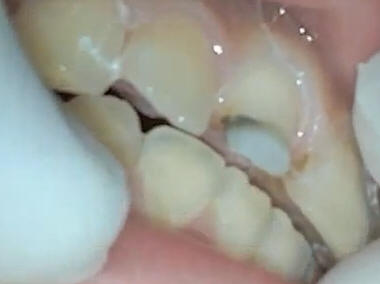

Reducción del borde

incisal |

Dejar suficiente espació

para la porcelana por lo menos 2 mm o más |

Ver el hombro realizado

en palatino que debe ser supragingival |